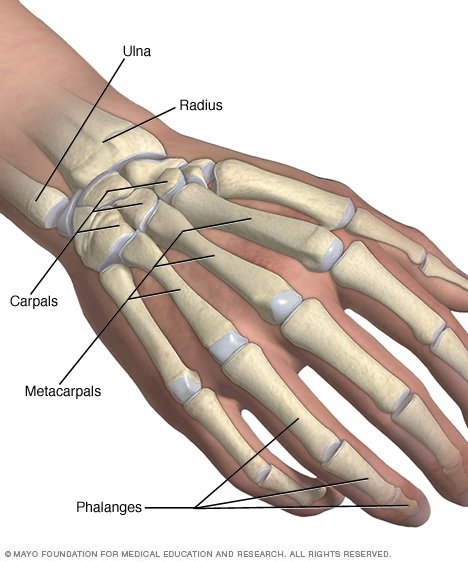

List showcases captivating images of what does a broken wrist look like pictures galleryz.online

what does a broken wrist look like pictures